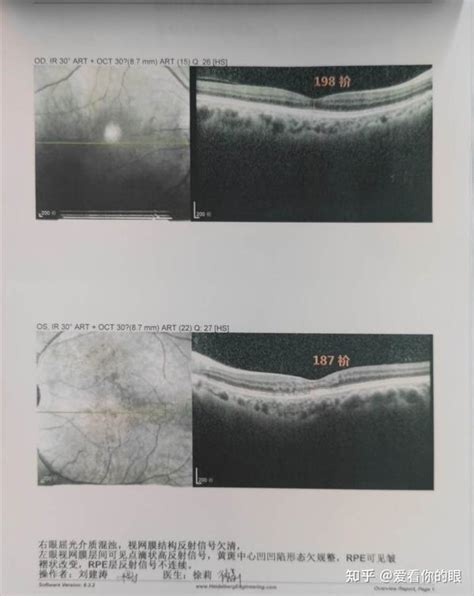

黄斑测试图图片